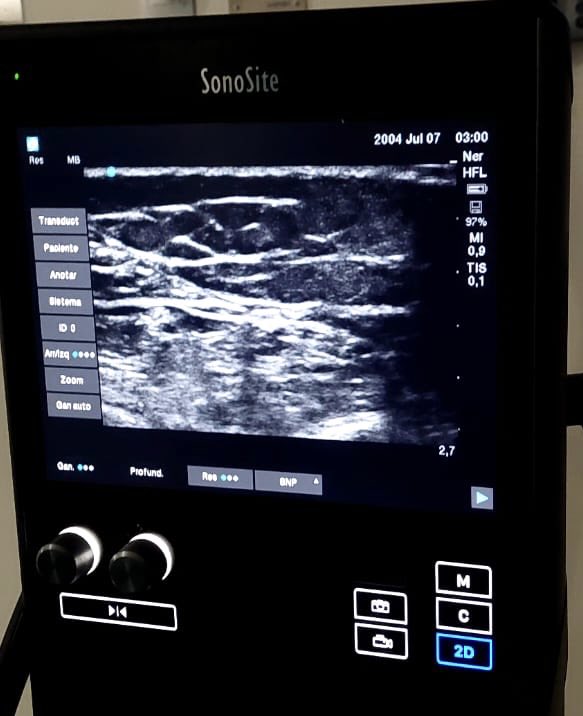

De vuelta a la lucha contra el dolor. Electrodo de ganglio para dolor de pared abdominal una muy buena alternativa al uso de opioides.